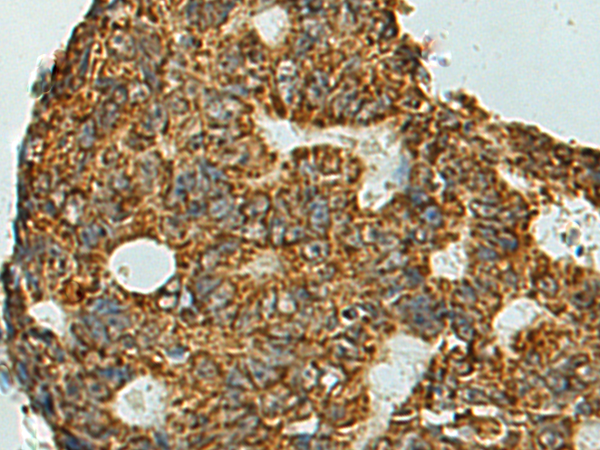

分类: 科研抗体货号: P11028别名: DJS; MRP2; cMRP; ABC30; CMOAT应用: IHC反应种属: Human